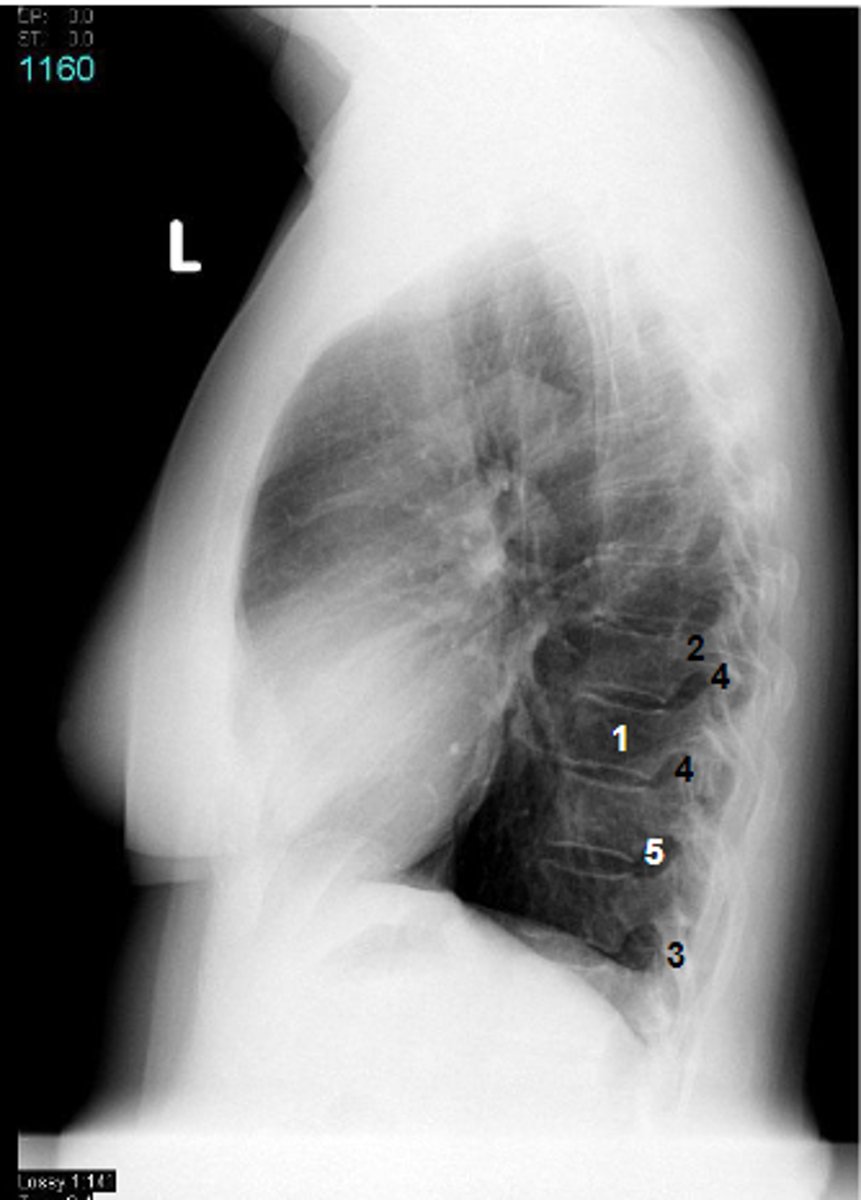

1

at what number is the trachea

2

at what number is the left main bronchus

3

at what number is the right main bronchus

4

at what number is the left superior lobar bronchus

5

at what number is the left inferior lobar bronchus

6

at what number is the right superior lobar bronchus

7

at what number is the right middle lobar bronchus

8

at what number is the right inferior lobar bronchus